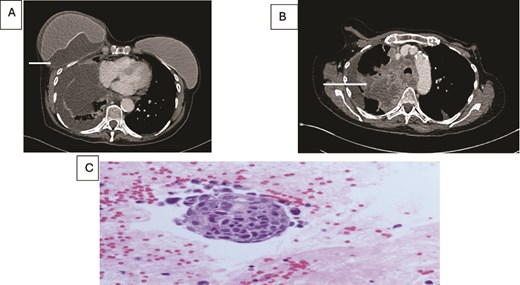

(A) Axial contrast enhanced CT shows right hilar mass. (B) CT scan showing bilateral breast metastasis (arrow) and left breast implant (arrowhead). (C) Cores of breast tissue infiltrated by malignant cells with high nuclear: cytoplasmic ratio, inconspicuous nucleoli and nuclear molding. The appearances are of small cell carcinoma.